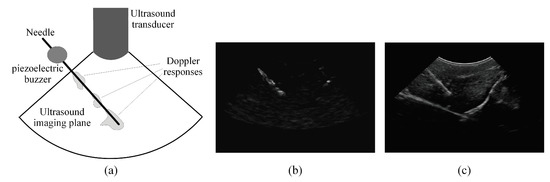

2.2. Analyzing the Power Doppler Ultrasound Image to Obtain an Initial Estimation of the Needle Axis and Identify the Candidate Regions of the Needle

2.3. Analyzing the B-Mode Ultrasound Image to Obtain Accurate Localization of the Needle Axis

2.4. Analyzing the Power Doppler and B-Mode Ultrasound Images to Obtain Accurate Localization of the Needle Tip